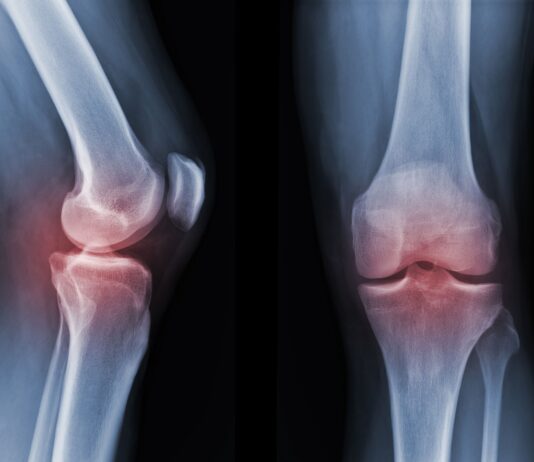

Artrosi: quanto aiuta davvero l’esercizio fisico

Un revisione sistematica coordinata dalla Bochum University of Applied Sciences, in Germania, e del Copenhagen University Hospital Bispebjerg Frederiksberg di Copenhagen, in...